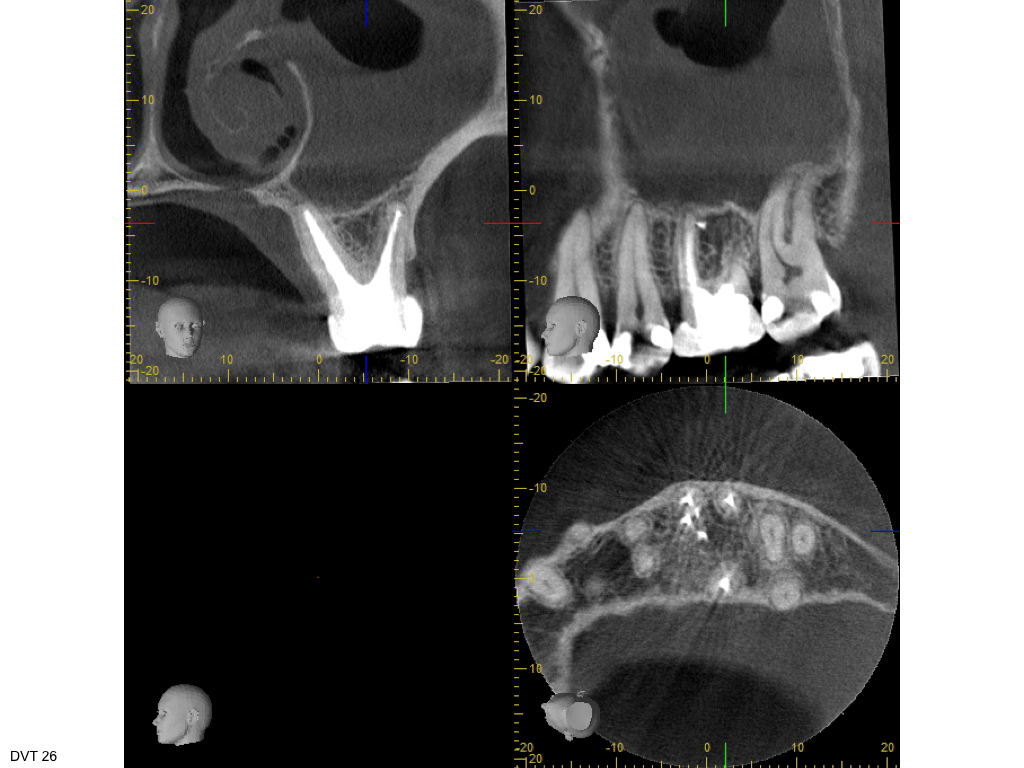

Heilung oder was?